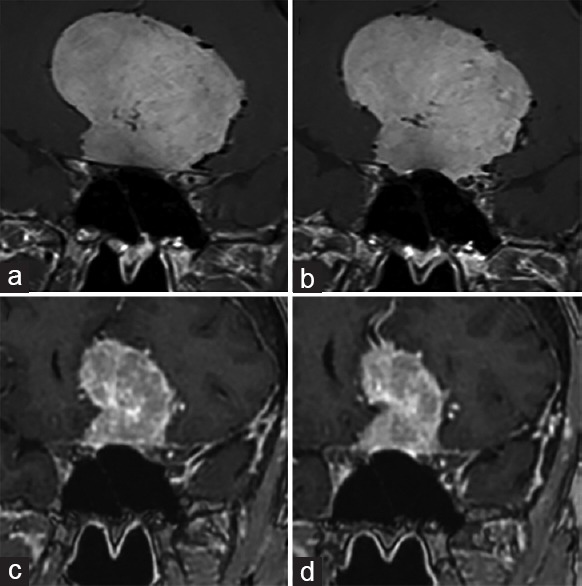

较大嗅沟 脑膜瘤 的消退及停药后视力的完全恢复 (Regression of Giant Olfactory Groove Meningioma and Complete Visual Acuity Recovery after Discontinuation of Cyproterone Acetate) 英...

OGM(嗅沟脑膜瘤)是良性的、生长缓慢的肿瘤,通常具有隐匿的非特异性症状,如头痛、嗅觉功能障碍、精神症状如抑郁、人格改变、认知功能下降、视觉...